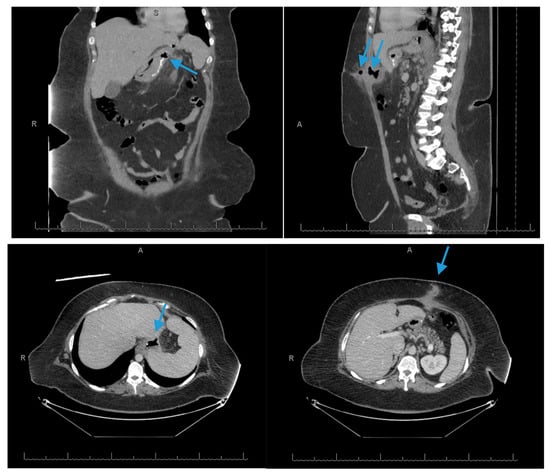

Scheme 1.

Lateral and transverse (top left and top right) views of a computed tomography scan of the abdomen and pelvis reveals air-fluid collections adjacent to the fundus of the stomach (3.3 × 3.0 cm) (arrow, top left), anterior to the stomach (2.2 × 4.6 cm) and in the epigastric region of the abdominal wall (6.2 × 3.0 cm) (arrows, top right), which likely represents abscesses in the setting of staple line dehiscence. Axial views of the computed tomography scan of the abdomen and pelvis (bottom left and bottom right) redemonstrate the somewhat ill-defined collection of gas and (arrows, bottom left and bottom right) fluid likely due to focal dehiscence and an abscess cavity which is the source of a gastrocutaneous fistula.